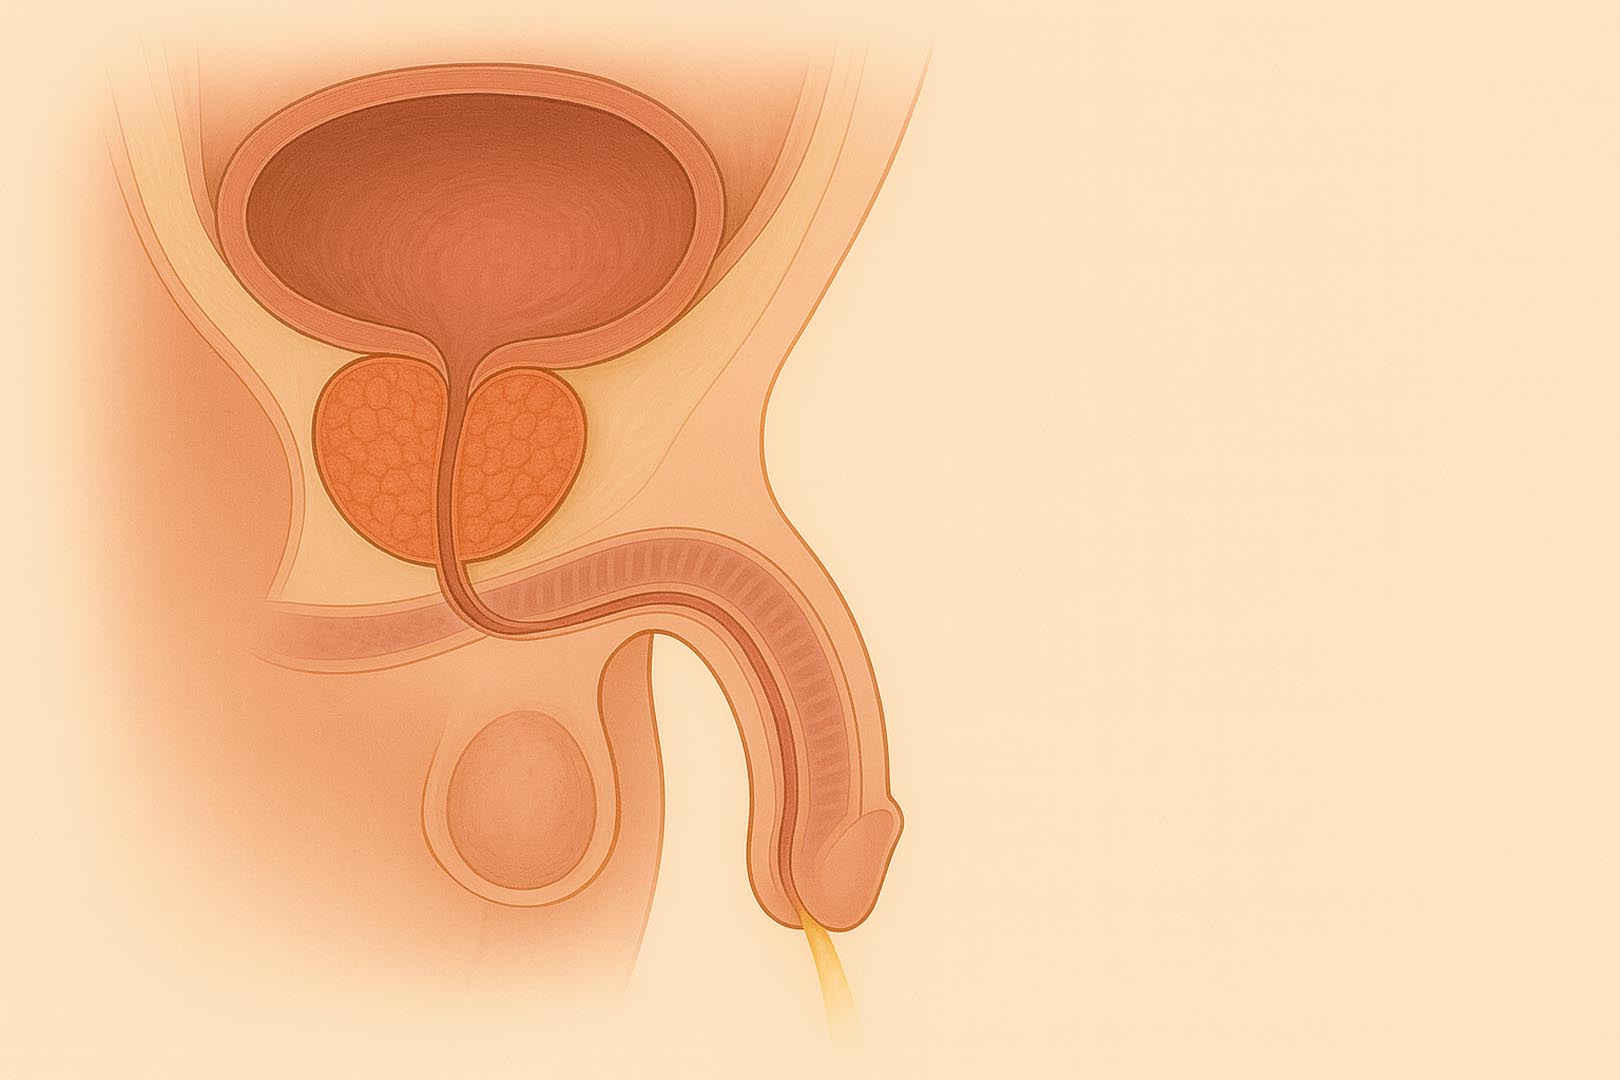

Un percorso completo e personalizzato per il trattamento dell'ipertrofia prostatica benigna attraverso tecnologie mini-invasive e altamente selettive, scelte in base alle tue caratteristiche cliniche specifiche.

Rezum™ Therapy - Vapore Acqueo Termico

Tecnologia a vapore che riduce selettivamente il volume della prostata. Trattamento ambulatoriale in pochi minuti, nessuna incisione, recupero rapido. Mantiene intatta la funzione sessuale.

TPLA - Terapia Termica Laser Percutanea Ecoguidata

Innovativa tecnica percutanea sotto guida ecografica. Esegue una necrosi controllata della porzione centrale della prostata. Indicato per prostate anche voluminose. Non necessita di resezione né cateterismo prolungato.

Green Laser - Vaporizzazione Fotoselettiva della Prostata

Tecnica endoscopica laser con vaporizzazione precisa. Ideale per prostata fino a 80-100 cc. Efficace nel ripristinare il flusso urinario. Minimo rischio emorragico, anche in pazienti anticoagulati.